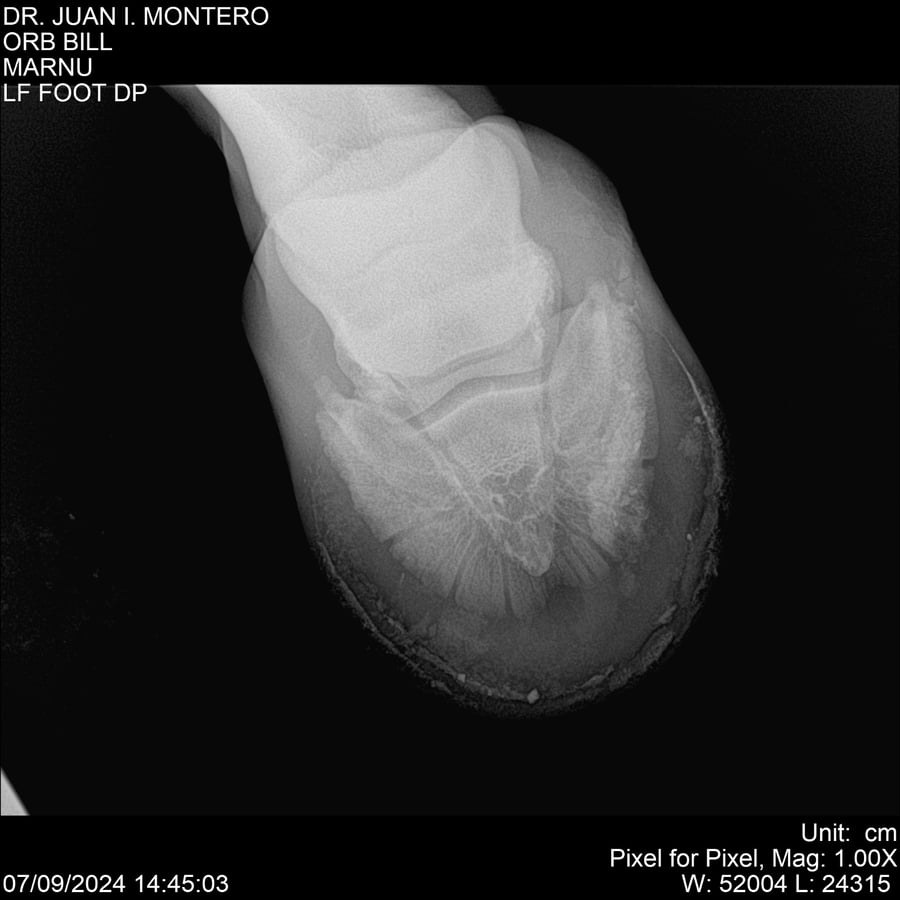

LOTE 7, ORB BILL 🔥 🔥 🔥 Lote Anterior Volver al remate Lote Siguiente Ficha Contacto Montevideo - Ficha del Lote Identificador: #282523 Categoría: Yeguarizos Montevideo - 83 Visualizaciones ClicData Contacto Empresa: Abelenda N. R., Walter Hugo Nombre*: Teléfono* : E-mail* : Mensaje Enviar Registrese gratis Este contenido Exclusivo está disponible sólo para usuarios registrados Ingresar